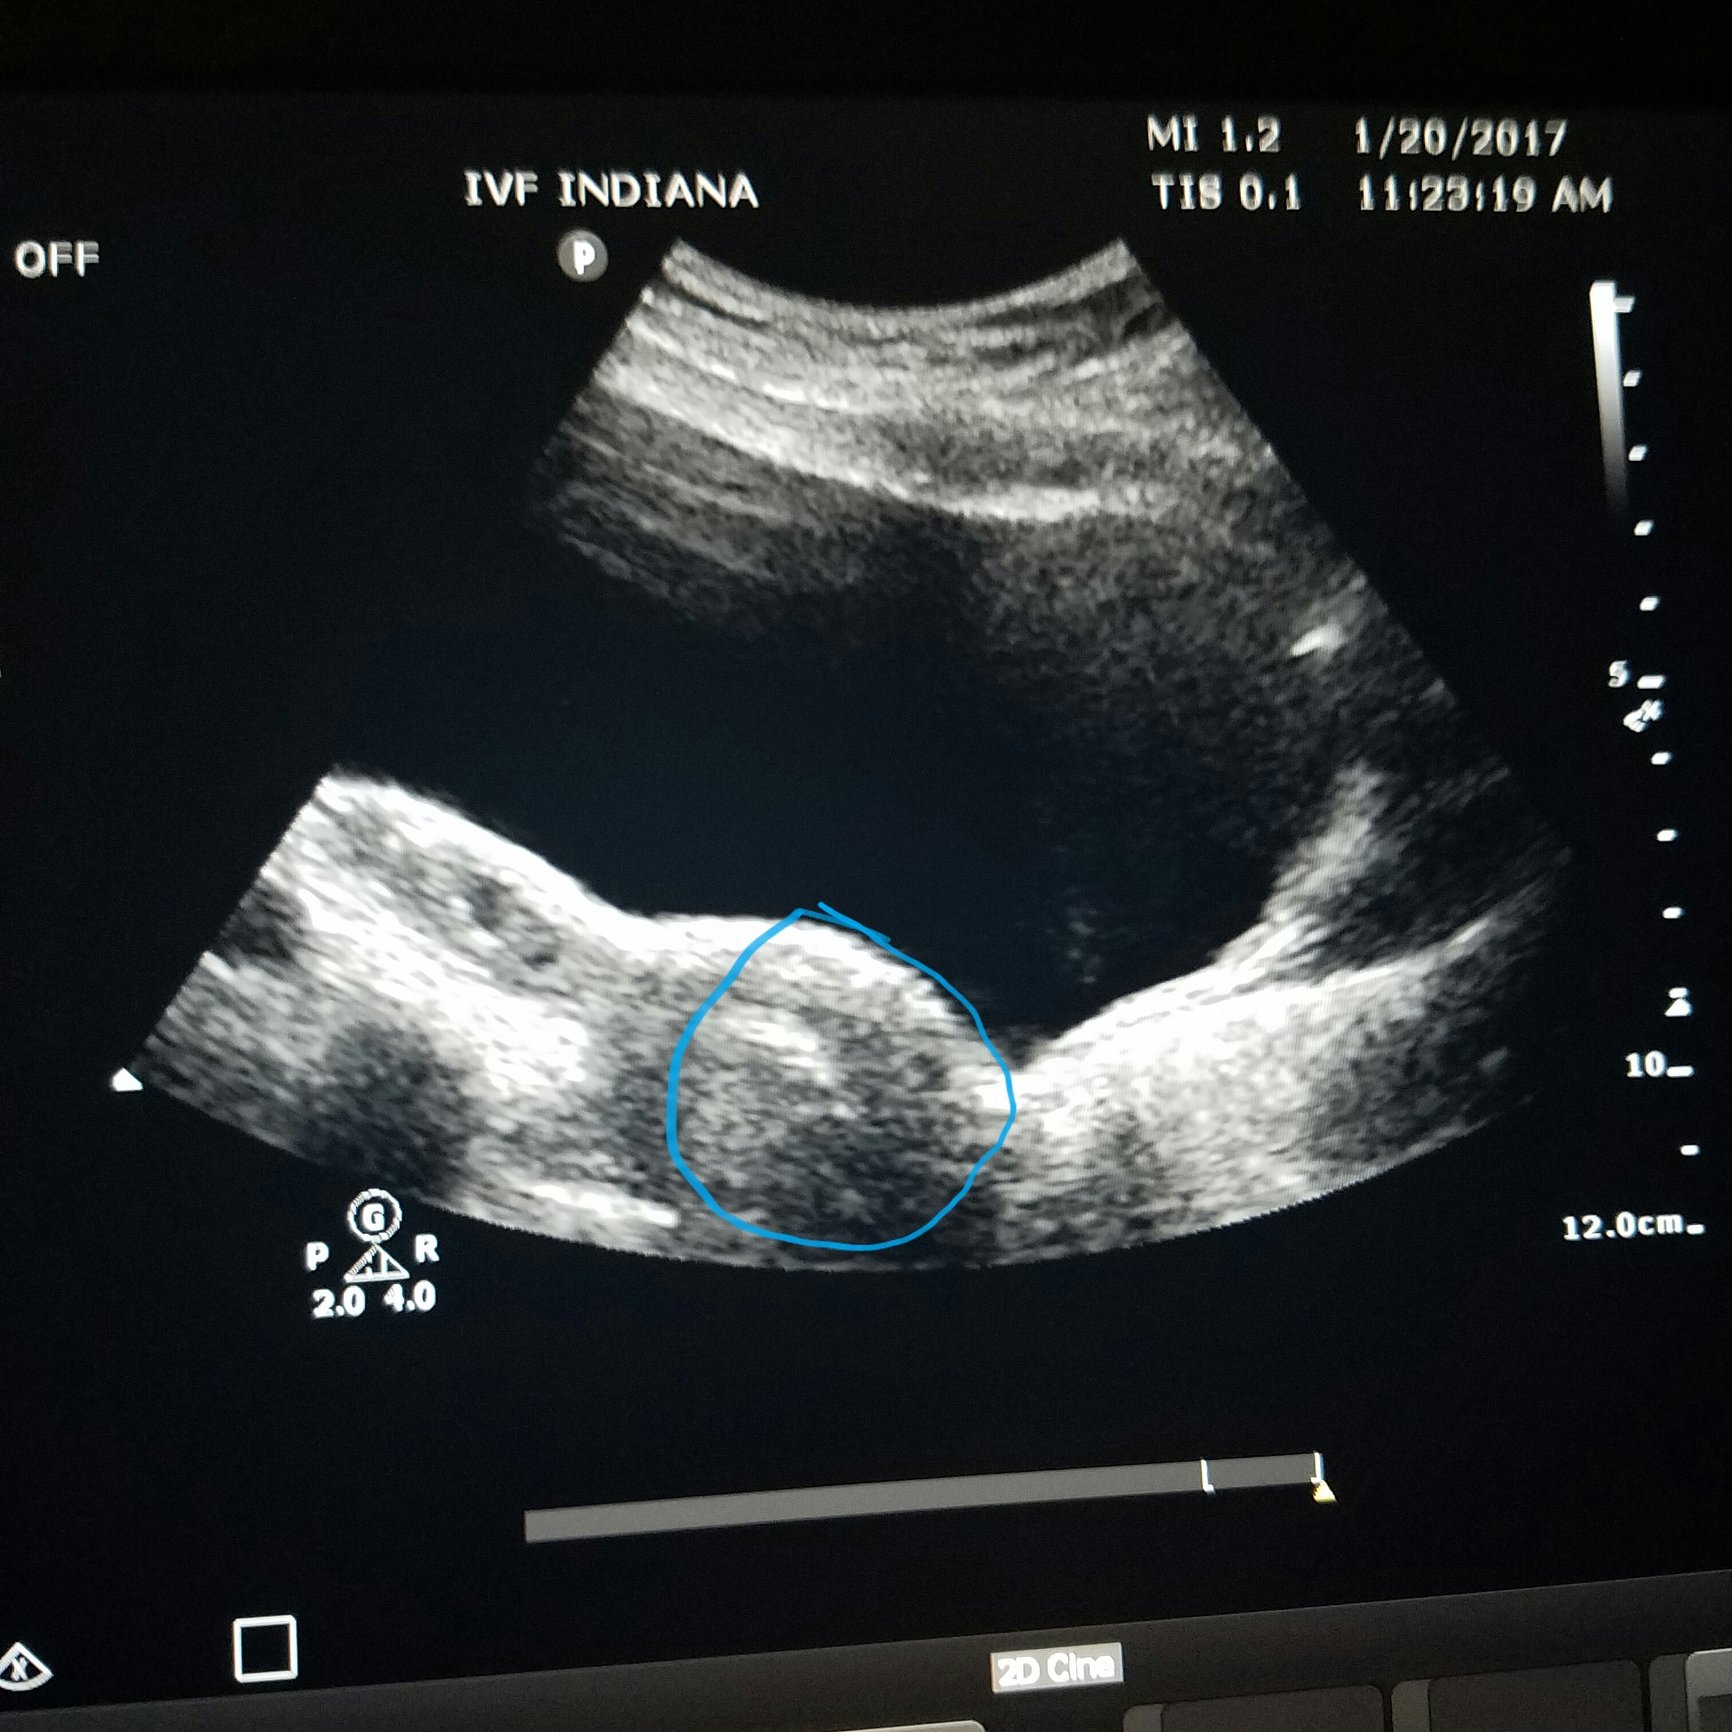

Welp I'm done. A nervous wreck and my DH is asking for a stiff drink and some time at the casino. The embroyologist came in. 1 was expanding the other not so much. After she left DH said f it just transfer both. Called my RE in for advice and he said let's do this. So we did it we transferred 2!!!!! Ahh!!! I'm not suppose to tell anyone and I just lied to my bestie but here we go. The decision of 1 or 2 is harder when you already have 2.

Me: 33 DH: 39 Me: Endo, PCOS, DH: low life span and mobility Married and TTC since 12/2008 3 IUI's in 2012 IVF #1 BFN 08/2012 IVF #2 11/2012 Twin Girls born at 35wks 7/2013 ER 4/2016 Freeze all 11 embryo's FET #1 5/2016 Transfer 1 BFN FET #2 7/2016 Transfer 1 BFN FET #3 09/2016 Thawed 3 Transfered 1 CP FET #4 1/2017 Transfer 2 CP FET #5 April 24, 2017 Transfering 1 BFN FET #6 June 8, 2017 Transfer 2 Beta #1 721 Beta #2 1363 US on 7/5 1 baby found EDD 2/24/18